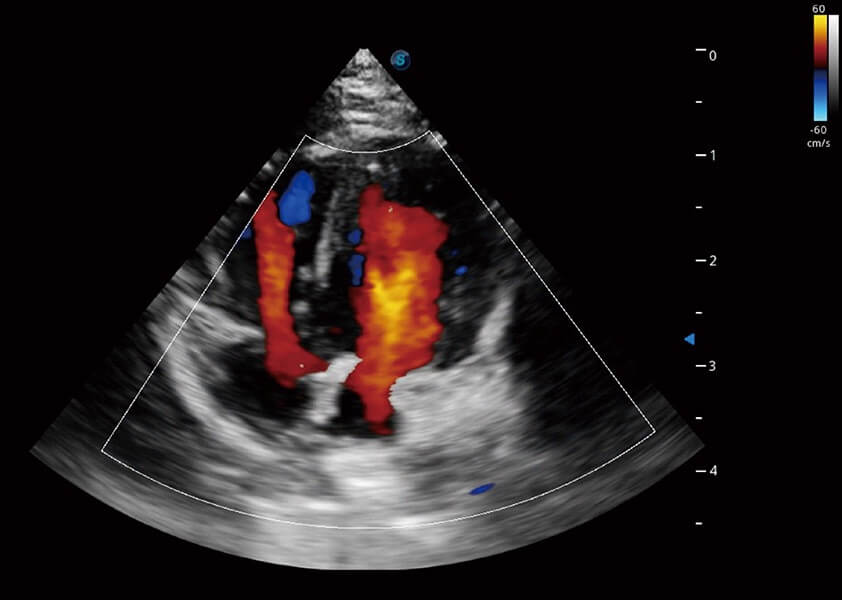

4T血流成像 微察秋毫

融合不同血流成像技术的优势,即可以提升血流成束性,同时可提高血流的视觉敏感性。

Bright Flow 立体血流成像

在传统二维血流成像的基础上,呈现血流的立体感,具有动感的生命力之美。精确区分不同血管的空间关系,提高了血流的视觉敏感性。

优异的基础图像

(犬)四腔心血流